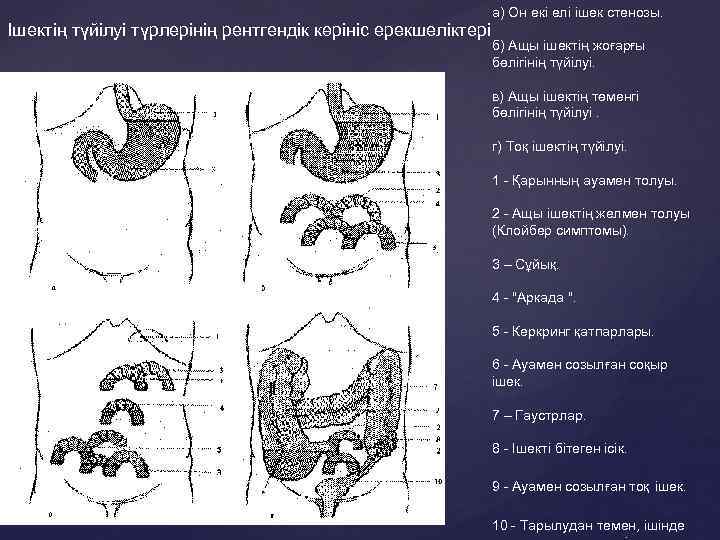

а) Он екі елі ішек стенозы. Ішектің түйілуі түрлерінің рентгендік көрініс ерекшеліктері б) Ащы ішектің жоғарғы бөлігінің түйілуі. в) Ащы ішектің төменгі бөлігінің түйілуі. г) Тоқ ішектің түйілуі. 1 - Қарынның ауамен толуы. 2 - Ащы ішектің желмен толуы (Клойбер симптомы). 3 – Сұйық. 4 - "Аркада ". 5 - Керкринг қатпарлары. 6 - Ауамен созылған соқыр ішек. 7 – Гаустрлар. 8 - Ішекті бітеген ісік. 9 - Ауамен созылған тоқ ішек. 10 - Тарылудан темен, ішінде